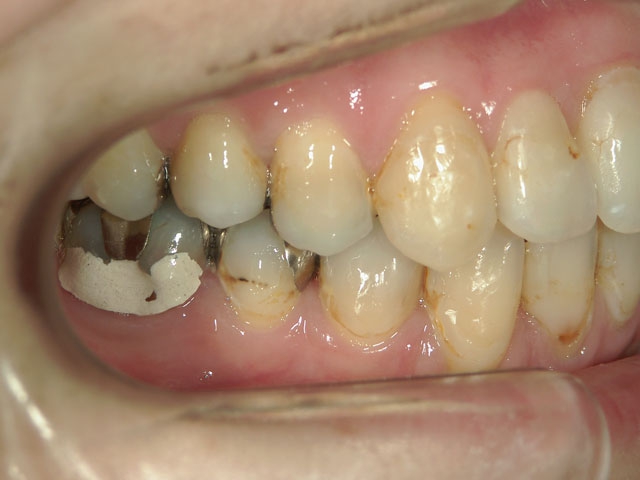

no.7_6967_治療前_右_01.jpgno.7_6967_治療後_正面_01.jpgno.7_6967_治療前_左_01.jpg

no.7_6967_治療後_右_01_640_480_やや高画質.jpgno.7_6967_治療後_正面_01.jpgno.7_6967_治療後_左_01.jpg